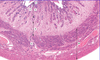

Which organ is this?

Ovary

Describe the surface epithelium of the ovary?

Simple squamous or cuboidal

Continuous with mesothelium

Tunica albuginea beneath it

70% ovarian tumours arise here

Describe the tunica albuginea of the ovary?

Beneath the surface epithelium

Dense connective tissue

Oocytes deep to it